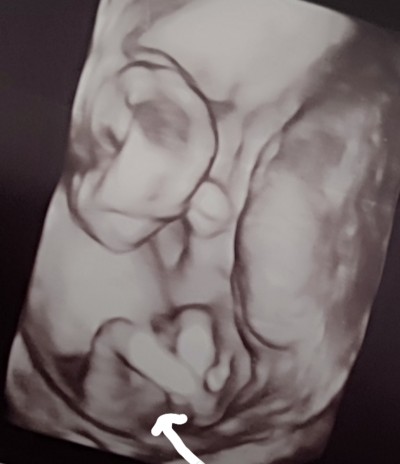

iki hafta önce çok iyi özel bir hastaneye gittim bana yüzde yüz erkek dedi eşime anlatıyorum belki değişir daha 14 haftaliksin dedi ultrason kağıdını gösterdim yanılmıyorsam bacak arası dolu sizde görüyor musunuz 😀 bence değismez artık ya bu arada iki hafta ilerde bebeğimin gelişimi o zaman gittiğimde de 16 haftalık gibiydi bebeğim karışıklıklara gelemiyorum net şeyleri severim bir defa yüzde yüz erkek dedi inşallah bir karışıklığın içine girmem daha siz ne düşünüyorsunuz kizlar

Gebelik haftası 16+3